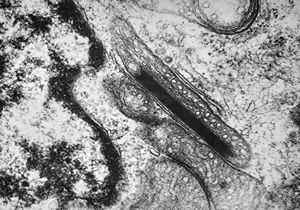

M,59y. | endothelial Weibel-Palade tubular body - angiomatous tumor, v.s.Kaposi